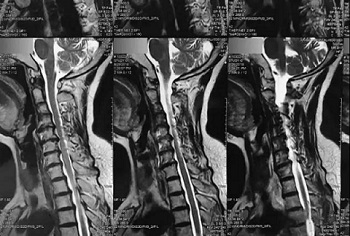

十一、将分区的磁共振图像,按顺序进行拍摄,即可获取如下比较有价值的清晰图片

十二、拍摄时,尽可能的将片子上的文字信息拍摄清楚,并将左右拍摄清楚(片子上有标R,表示右侧right,L, 表示左侧left的意思), 每张片子上的文字都能按照阅读习惯拍正确,不要拍反了。

拍摄时,必须要对着片子上的文字对焦, 方向正确,将文字拍摄得清晰可视,保证放大图片后文字依然清晰可见(如下图),尽可能多的保留片子上的信息。